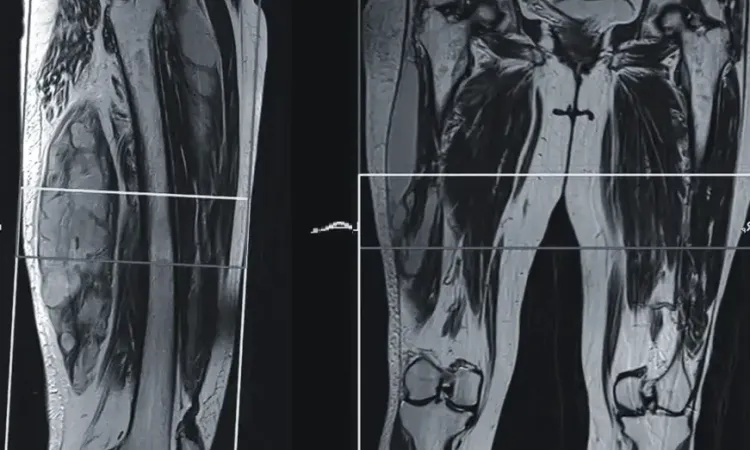

МРТ мягких тканей на Каширском шоссе в Москве применяется при подозрении на наличие каких-либо патологий. Оно используется для установления заболеваний кожи, подкожной клетчатки, сухожилий, суставных капсул, нервных и железистых тканей. Таким образом магнитно-резонансная томография выявляет изменения в мягких тканях человеческого организма, где отсутствует части костного скелета. Это исследование также активно применяется среди спортивных врачей. Они по МРТ отслеживают как протекает процесс восстановления у спортсменов после травм.

- Диагностика спортивных травм (повреждения плеча, колена, голеностопа).

- Контроль за состоянием мягких тканей после операций.

- Оценка посттравматических состояний и реабилитационного прогресса.